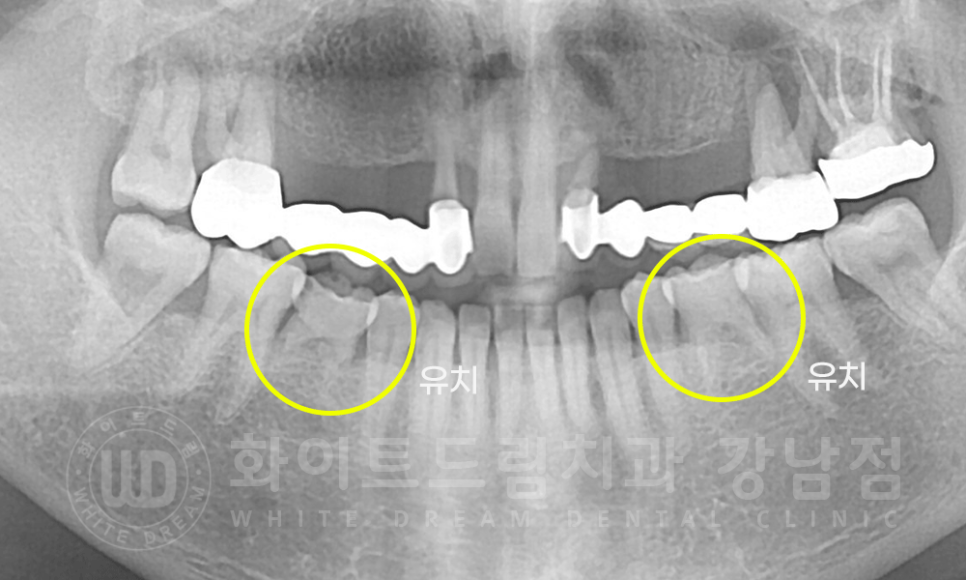

브릿지 외에도 한 가지 더 특이사항이 있었는데요.

환자분의 x-ray를 보면 뿌리가 유난히 짧은 치아가 2개 있습니다.

성인이 유치가 남아있다고?

이렇게 생각하실 수도 있는데, 선천적으로 영구치가 나오지 않아 성인이 된 후에도

유치가 남아있는 경우들이 종종 있답니다.

유치는 영구치에 비해 치아 뿌리가 짧기 때문에 강한 힘을 받으면 흔들리거나 손상될 확률이 큽니다.

조금만 조심히 사용을 해주시고. 딱히 문제가 없다면 사용 가능할 때까지 사용하시면 된답니다.

강남역 치과브릿지 / 치료 전 X-RAY